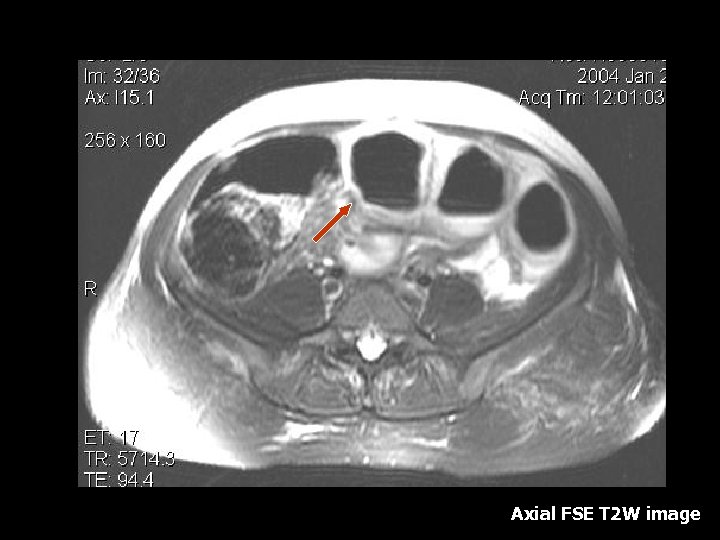

Large Leiomyoma • 25 -50% of women of child bearing age(6). • Composed of smooth muscle and variable amount of fibrous tissue, surrounded by a psuedocapsule of areolar tissue (6). • Hormonal stimulation due to pregnancy can cause rapid growth(6). • MRI findings: T 2 W images demonstrate a well circumscribed mass with predominantly low signal intensity (6). • T 1 weighted images show intermediate signal, often indistinguishable from surrounding uterine tissue(6). • Degenerative changes appear as high signal on T 2 weighted images(6). • Foci of calcifications appear as low intensity on all sequences (6).

Red Degeneration • Red degeneration of uterine leiomyoma is due to hemorrhagic infarction of the leiomyoma as a result of obstruction of peripheral drainage veins(2, 5). • Symptoms: Abdominal pain, fever and leukocytosis(2). • MRI: Peripheral rim shows Low signal intensity on T 2 WI and High signal intensity on T 1 WI(2, 5). • Signal intensity in the central portion is heterogeneous on T 2 W images and becomes gradually higher on T 1 W images (2, 5). • The entire mass does not show enhancement due to completely interrupted blood flow (5).